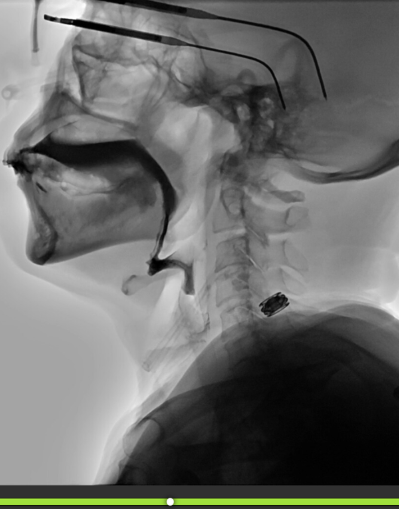

Number of Swallows Per Bolus

Quick Takeaways

Data obtained when completing the ASPEKT-C Method.

When assessing the number of swallows per bolus using the ASPEKT-C Method, a swallow is defined as UES opening plus at least one of the following: pharyngeal constriction, laryngeal elevation and/or hyoid excursion. Do not include swallow attempts.

Steps for Completion

Use frame-by-frame review with audio on to determine bolus administration.

Track the number of swallows per bolus.

Example: Patient swallowed twice with cup sip thin independently. Data obtained with frame-by-frame review and detailed using the Notes tool.